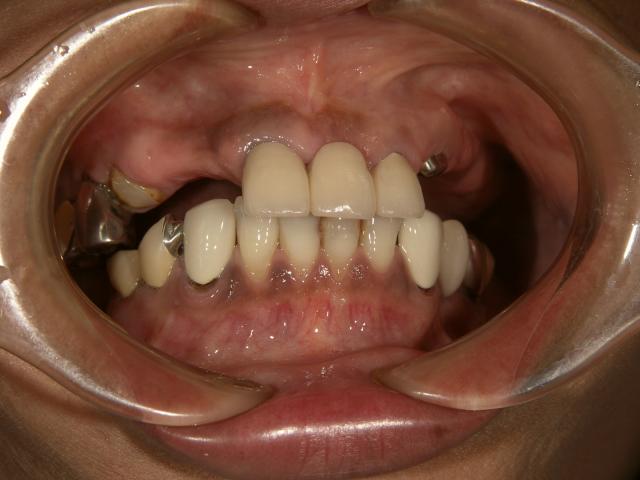

ノンクラスプデンチャー 金属の見えないようにしたい!!

2006/07/10

担当医;院長神保

50代後半女性 上の歯の見栄えを自然にしたい希望。

前歯3本 奥歯3本のみしか残ってませんでした。

上の歯の見栄えを自然に

前歯3本はセラミックス使用 義歯はノンクラスプデンチャー設計です。

入れ歯を入れているのが判らなくなりました!!

上の歯の見栄えを自然に 上の歯の見栄えを自然に

また入れ歯を外しても前歯が自然なので外食も怖くなくなったそうです。

よかったですね!!